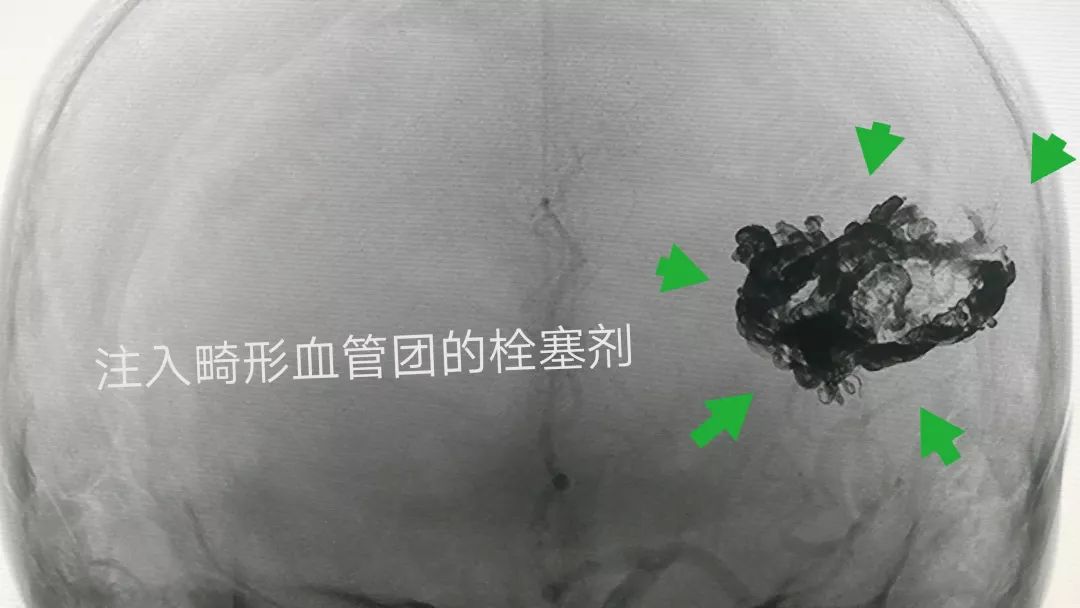

畸形团内注入的栓塞剂清晰可见(下图)